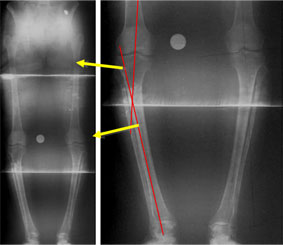

In the example shown here, the patient had a varus deformity of both tibiae (bow legs – reduced angle at the bone below the knee) with slight external rotation deformity of the tibiae (the feet pointing outward while the patellae [knee caps] face forward).

The deformities were corrected on both the sides acutely (at one go during surgery) and LRS (Limb Reconstruction System) fixator was applied on each side. |

The full length x-ray shows the seat of deformity as the upper tibial diaphysis (shaft). Femur on both the sides is normal.

The x-ray picture here shows the fibular and tibial osteotomies.

Both the deformities, angulation and rotation were corrected acutely on the operating table. Since the osteotomy was made at the level of CORA there was no translation at the osteotomy site.

The bone is held in the corrected position with a LRS fixator.

The corrected bone axis is shown by the yellow line. |